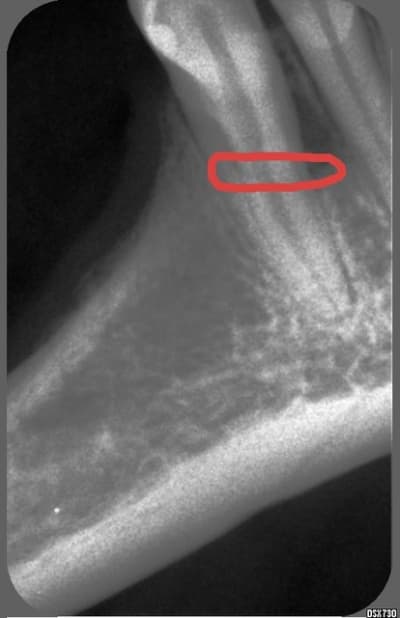

Et ça à votre avis c'est un artefact ?

Enigme d6tran - Eugenol

Et il ne devrait pas y avoir de douleurs face à une félure / fracture ? C'est vrai que ça y ressemble.

Je me méfie malgré tout des signes évidents, quand on cherche quelque chose, on finit par le voir.

Et est ce mes yeux ou est ce que j'ai l'impression d'imaginer supposément voir une 2 eme racine superposée, ou alors c'est une racine en huit en effet.